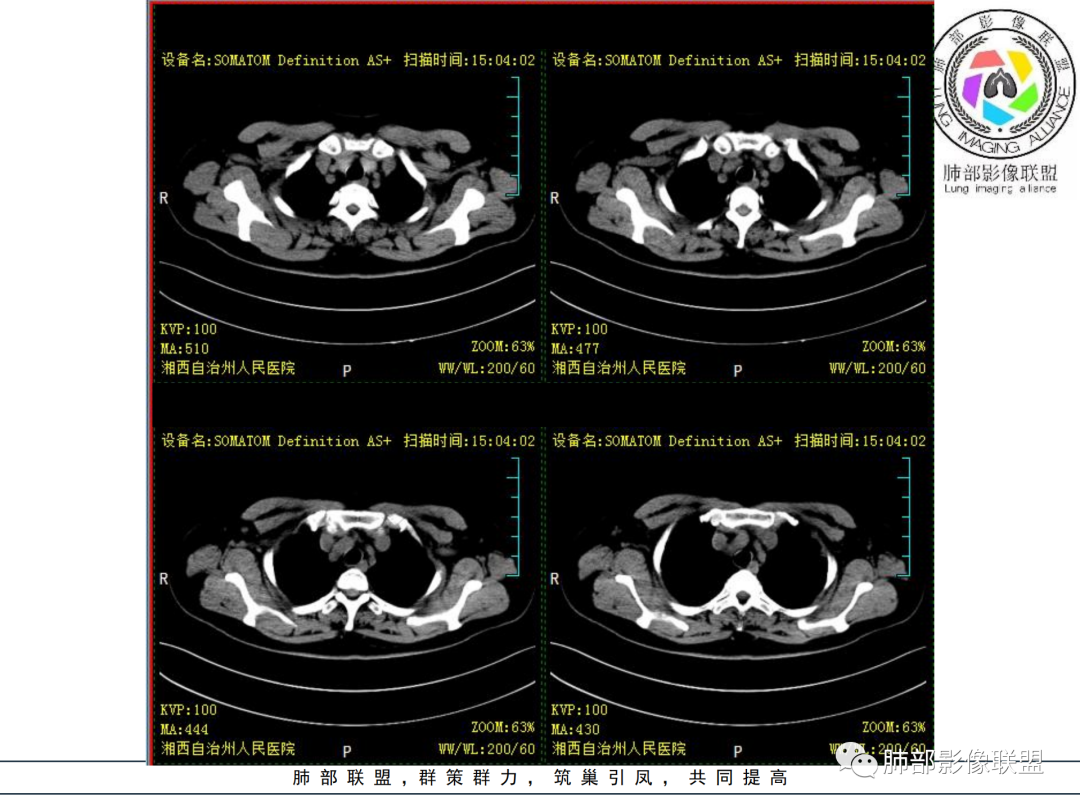

类风湿节关节炎(RA)累及胸部常出现胸膜病变、气道病变(支气管扩张、滤泡性支气管炎、闭塞性支气管炎等)、ILD、RA结节等。

RA胸膜病变HRCT表现为轻度胸膜增厚,少量、单侧的胸腔积液,胸腔积液多为自限性,不定合并肺内病变,气道病变通常为RA肺内最早出现的征象,约30%~58%的RA患者HRCT可见支气管扩张。闭塞性细支气管炎CT表现为马赛克征、小气道闭塞、支气管扩张,深呼气相呈可见空气潴留。滤泡性细支气管炎CT多表现为磨玻璃样密度的小叶中心结节。

1.中年女性,发现双肺多发病变,且增多增大。

缺乏呼吸道症状及中毒症状,实验室炎性指标不高

既往多关节肿痛一年余,被诊断“类风湿”。此次就医无关节肿痛。

2.双肺多发片状影,胸膜下分布为主,部分沿支气管血管束分布,边界不清,实性及磨玻璃密度,趋于柔和,可见支气管进入或穿行,未见空洞、钙化及树芽等。部分病灶显示反晕。

3.未见腔积液。

4.双肺门及纵隔未见增大淋巴结。